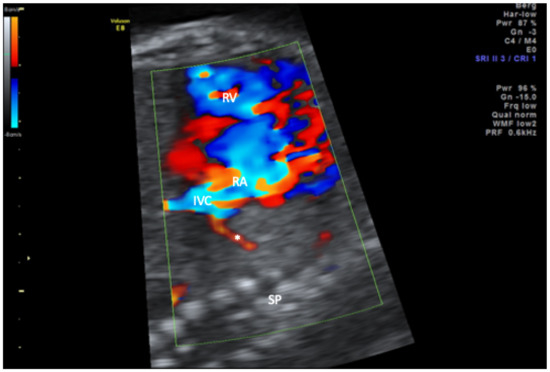

Scimitar syndrome is a rare disease characterized by hypoplasia of the right lung and partial anomalous pulmonary venous drainage to the inferior vena cava. All cases with a prenatal diagnosis of scimitar syndrome with or without associated malformations in an 18-year period (2000–2018) in two large tertiary referral centers (University of Bonn and University of Cologne, Germany) were retrospectively reviewed for the intrauterine course and postnatal outcome. Six cases were diagnosed in the study period. All presented with hypoplasia of the right lung, right-sided mediastinal shift, and abnormal pulmonary venous drainage to the inferior vena cava. Systemic arterial blood supply to the right lung, albeit postnatally present in all cases, could not be detected prenatally. Major associated anomalies were present in all cases and included atrial septal defect (n = 5), coarctation (n = 3), diaphragmatic hernia (n = 2), and VACTERL association (n = 1). Half of the cohort died within 6 months after birth and all three survivors suffer from long-term pulmonary sequelae. The primary hint to the prenatal diagnosis of scimitar syndrome is the abnormal position of the heart in the chest. If searched for, abnormal venous drainage can be identified prenatally and confirms the diagnosis. The prognosis depends on the presence of associated major anomalies and the need for neonatal intervention. Full article

Figure 1